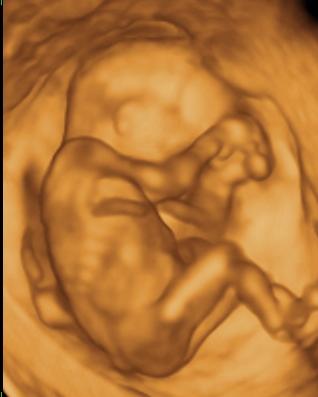

Nagyon boldog névnapot a pici fiúnak!